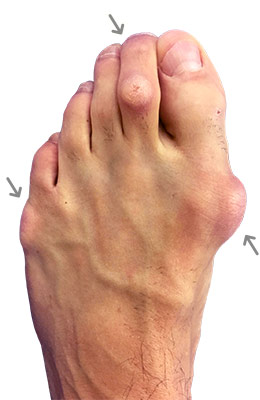

Lapidus Forever Bunionectomy™ and Hamertoe Correction

Amanda is a 37-year-old mother who could not take much time off her foot and needed correction of a very large bunion (hallux valgus) that had also resulted in a hammertoe and partial discoloration of the 2nd toe joint. Amanda had a Lapidus Forever Bunionectomy™ and was back on her foot at 2 weeks after surgery and able to take care of her young children while she healed. Her bunion correction results are amazing, and her foot is fully back to normal.